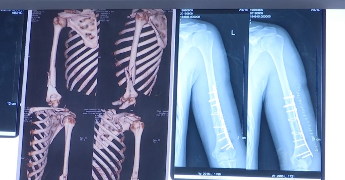

“拍了片子以后大家都大吃一惊,整个肱骨粉碎性骨折!”武进人民医院骨科主任历晓龙介绍。

通过X片可以看出,许同学骨折极其明显,骨头断为两截。